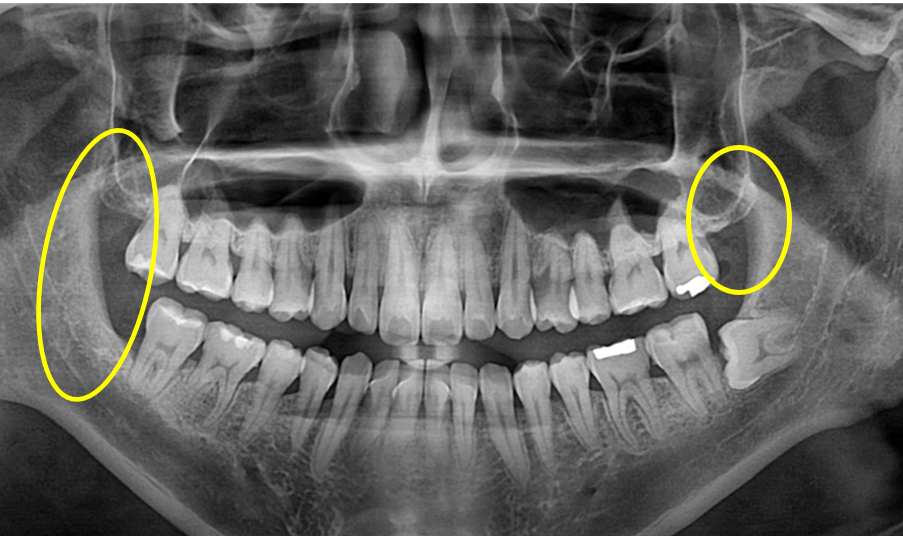

상,하악 사랑니 발치

Before

아예 잇몸 깊숙히 누워있는 사랑니는 굳이 발치하지 않아도 되지만,

잇몸 밖으로 부분적으로 나온 사랑니들은 관리하기도 어렵고

앞 치아와의 사이에 음식물이 끼어 앞 치아까지 망가질 수 있으므로 발치가 필요합니다.